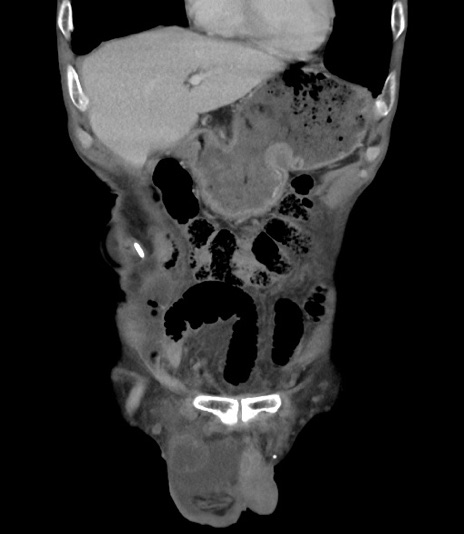

症例3(冠状断像)

【症例】 70歳代男性

【主訴】右鼠径部腫瘤、疼痛

【現病歴】本日朝より上記主訴あり、受診。

【既往歴】膀胱癌にて膀胱全摘、両側尿管皮膚瘻

【データ】WBC 5600、CRP 0.56